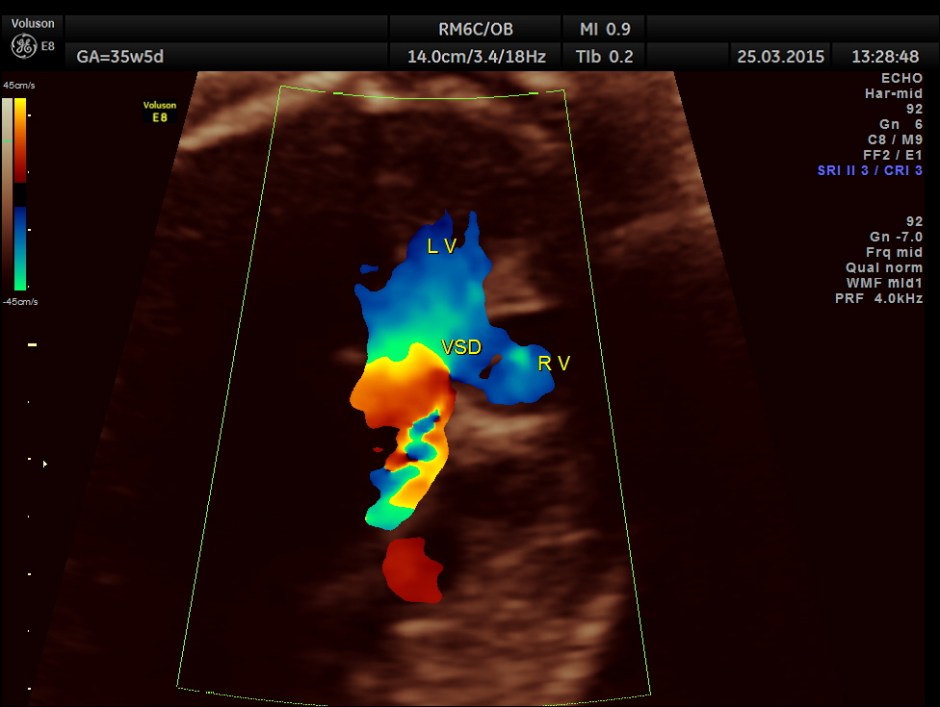

Ventricular Septal Defect is seen.

Ventricular Septal Defect is seen .